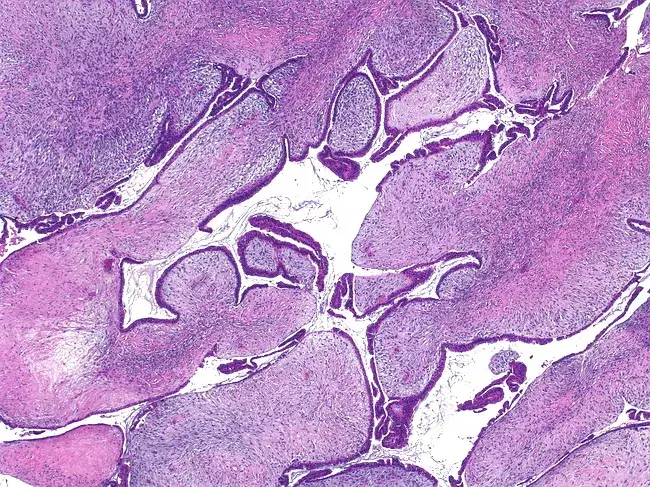

Depending on the type of growth, the histological variants of fibroadenomas are as follows:

• Pericanalicular: characterized by the growth of connective tissue around the mammary ducts while maintaining their patency;

• Intracanalicular: connective tissue growth occurs inside the duct, leading to its deformation and narrowing of the lumen up to complete occlusion;

• Mixed fibroadenoma: connective tissue growth occurs both around and inside the ducts.

Pericanalicular fibroadenoma

Pericanalicular fibroadenoma. Source: WebPathology [11]

Intracanalicular fibroadenoma.

Intracanalicular fibroadenoma. Source: WebPathology [11]

Below are histological images of low-grade phyllodes tumors (fibroadenomas) having various manifestations and histological changes. Source: WebPathology [11]: